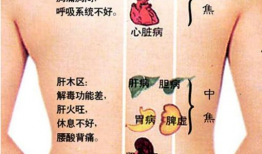

怎么刮痧背部视频教程,轻松掌握背部刮痧技巧

你有没有试过那种感觉,背上的肌肉像是被小怪兽抓挠,又酸又痛,让人坐立不安?别担心,今天我要给你带来一个超级实用的技能——刮痧!刮...